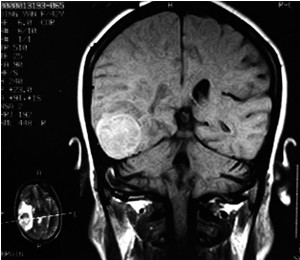

3、CT扫描:示局部有低密度区(CT值近似脑脊液密度),边界清楚。注造影剂后无囊壁增强。本症应与脑穿通畸形及颅内上皮样或皮样瘤鉴别。前者为脑组织缺失,脑脊液充填空腔,故腔与脑室或蛛网膜下腔自由交通,CT扫描可以鉴别。颅内上皮样或皮样瘤在CT扫描时与本症相同均示低密度区,但其边缘较模糊,外侧壁与颅骨内板间常有一段距离,且形状不规则。其他尚应与慢性硬膜下血肿或水瘤鉴别。